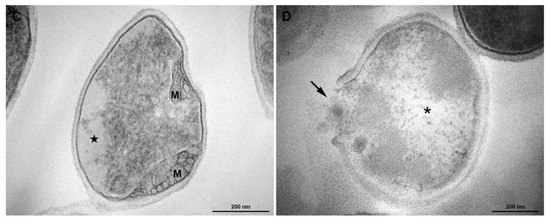

3.5. Transmission Electronic Microscopy